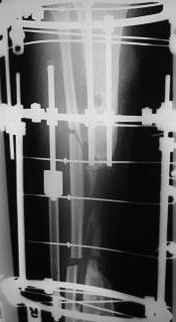

Dear Dr. Firas

You can do it like this also...